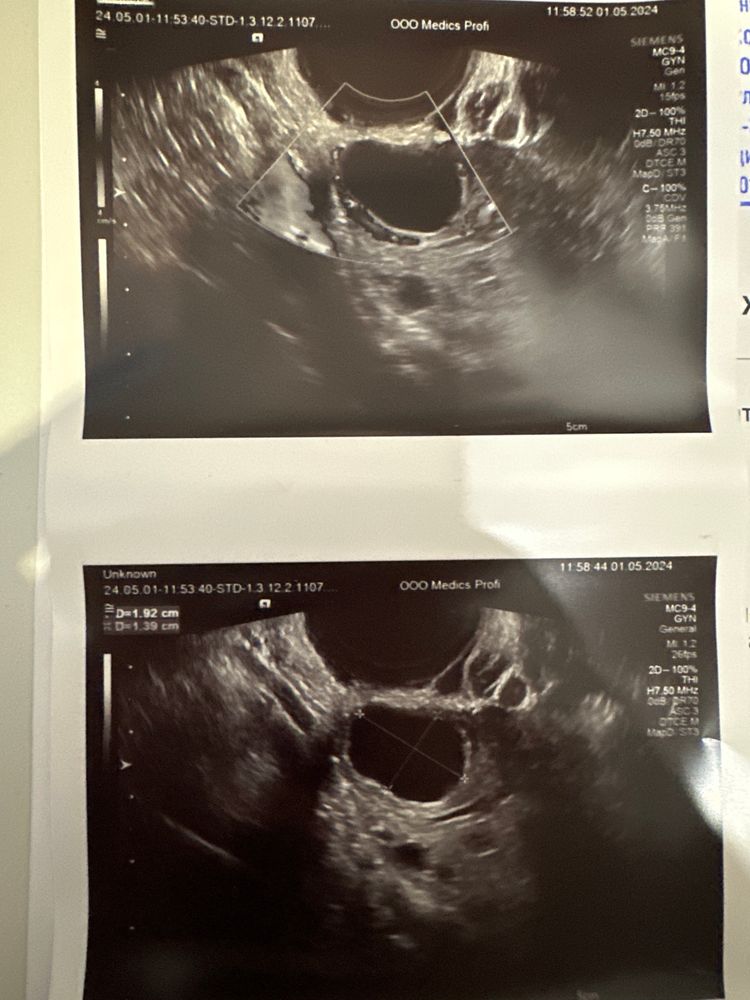

Гинекологи разводят руками, кто то ставит МФЯ, кто-то СПКЯ. Последний гинеколог назначила дюфастон по 1т 2р день с 11дц по 26.. без узи и подтвержденной о . пропила 1 месяц , ужасная побочка в виде боли в груди и животе . В этом месяце решила не пить с 11дц а походить на фолликуломктрию сама , итого что имеем на 10 дц - фолик 11 в левом и 14 мм в правом . 13дц- фолик 22мм в левом ( узистка удивлена, я тоже) говорит по размерам как будто мой цикл 28 дней . 14дц перед узи очень сильно ноет левый яичник , прихожу на узи - фолик 27мм😳. Говорит скорее всего киста будет . Я в расстроенных чувствах, боль не отпускает . Спустя часов 5 тянущей боли резко кольнуло и отпустило насовсем , ( раньше я никогда не ощущала овуляцию) , сегодня 15 дц- говорит уменьшился Твой ДФ , 19 мм стал , я ничего не понимаю , как так 🫣 говорит скорей всего была овуляция , но она не уверена , ну а я тем более ничего не понимаю в узи , говорит жидкость есть и кровоток хороший в общем сказала прийти на 21 дц что бы увидеть жт если это была овуляция . Может кто то разбирается в узи?